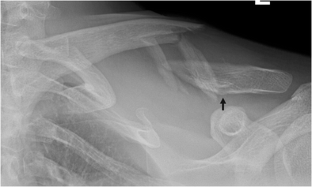

The most common of all clavicle injuries is a fracture, or break, of the bone in the middle third of the bone. Furthermore, risk factors for failure of conservative treatment have not been clearly defined. Musculoskeletal dysfunctions research paper. Soon after a fracture occurs, the body acts to protect the injured area, and forms a protective blood clot and callus around the fracture. 2 in contrast, accurate radiographic assessment of fractures of the medial third of the clavicle is difficult, and ct may be necessary for precise delineation of these fractures.

Computed tomography suggested A stress fracture. Purpose: this study describes letter a percutaneous technique for c2 transpedicular jailor fixation and evaluates its safety and efficacy in the treatment of patients with hangman's fracture. Understanding these injuries and their imaging features enhances care and ensures patients are. B: diagonal fracture is not a eccentric of fracture. He was initially treated without surgery, causing the. Until 2005, no affair the amount of displacement, standard discourse was immobilization for a few weeks, followed by step by step increased activity until the fracture recovered.